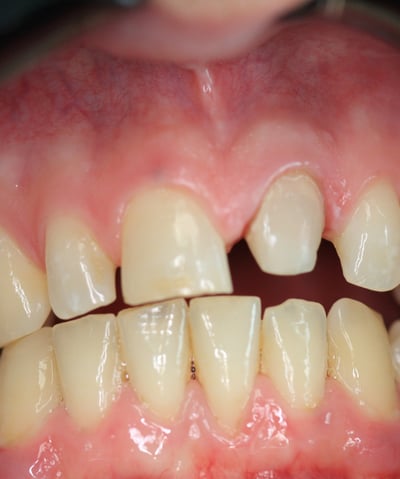

4. Prova Estetica e Cementazione della Corona Definitiva

La corona definitiva in disilicato di litio è stata progettata per mimetizzarsi perfettamente con i denti naturali in termini di colore, traslucenza e forma. Dopo una prova estetica accurata, la corona è stata cementata utilizzando un cemento adesivo di ultima generazione, garantendo un'adesione duratura e stabile

Corona Estetica

Condizioni Finali

La sostituzione della corona su un incisivo centrale richiede un approccio multidisciplinare che coniughi precisione clinica ed eccellenza estetica. In questo caso, il ritrattamento endodontico, la sostituzione del perno moncone e la realizzazione di una nuova corona in disilicato di litio hanno permesso di ottenere un risultato ottimale sia dal punto di vista funzionale che estetico.

Grazie all'impiego di materiali avanzati e tecniche minimamente invasive, è stato possibile garantire al paziente una riabilitazione duratura, ripristinando la stabilità protesica e l’armonia del sorriso. Questo caso conferma l'importanza di una diagnosi accurata e di un piano di trattamento personalizzato per risolvere definitivamente le problematiche legate alle corone incongrue.